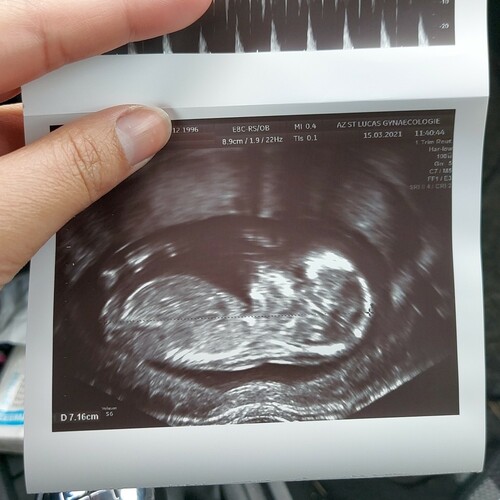

13 weken ongeveer op de foto en bijmij is het een meisje en ik denk een jongen bij jou 😊 en bijmij duurde het 7 dagen. Had het via email gekregen toen

Dinsdagochtend bloed geprikt en de week erna donderdagmiddah resultaat op Cozo. Wel paasweekend ertussen! Echo van 11 weken en 6 dagen. We krijgen een meisje! 💕💕